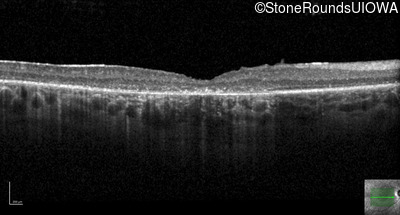

Optical Coherence Tomography - Left - 20/125 -1

Exemplar / OCT Stack

OCT Stack